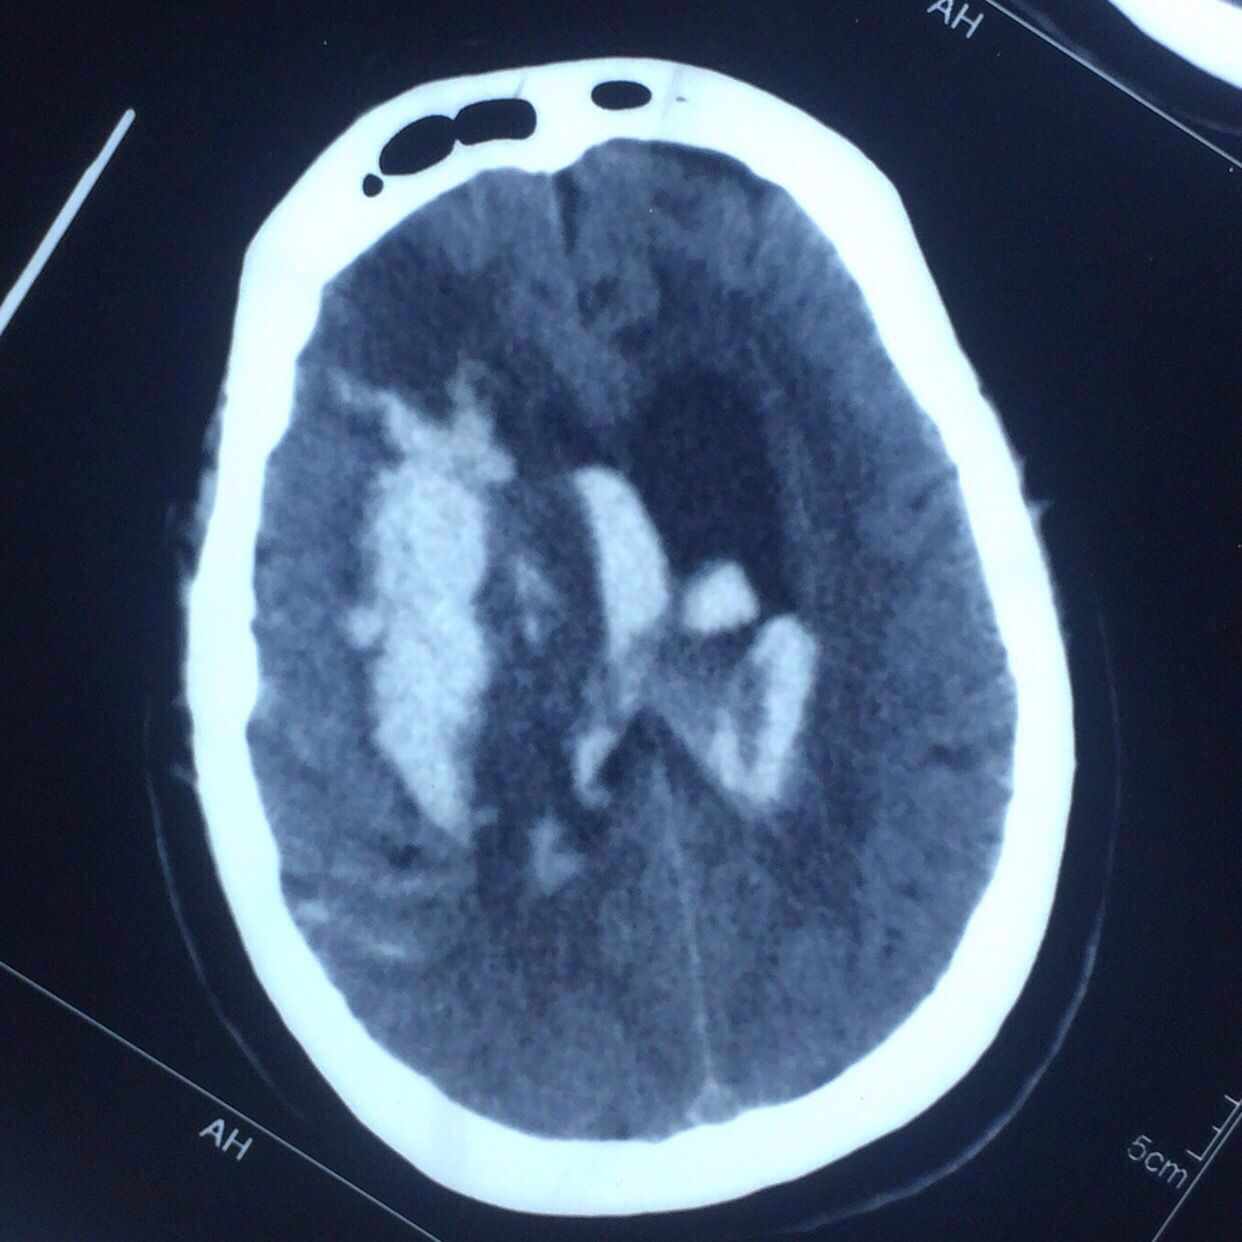

CT片见上图:

右侧基底节出血破入脑室脑积水